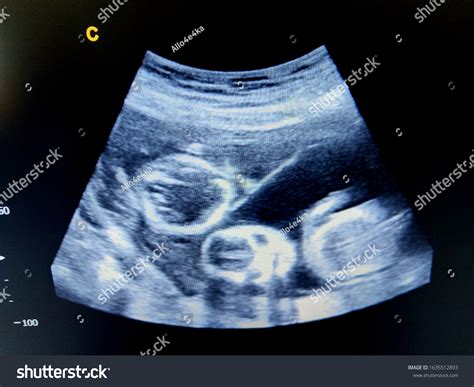

Embarking on the journey of parenthood is an exciting and transformative experience, especially when expecting twins. One of the most crucial milestones in this journey is the Ultrasound 9 Weeks Twins scan. This early ultrasound provides invaluable insights into the development and health of the twins, offering parents a glimpse into their babies' world. Understanding what to expect during this ultrasound can help alleviate anxieties and prepare parents for the road ahead.

The Ultrasound 9 Weeks Twins scan is typically performed between 8 and 10 weeks of pregnancy. At this stage, the embryos are still very small, but significant developments are occurring. The primary goal of this ultrasound is to confirm the presence of two gestational sacs, each containing an embryo. This confirmation is crucial for determining the type of twin pregnancy—whether it is dizygotic (fraternal) or monozygotic (identical).

During the Ultrasound 9 Weeks Twins scan, the ultrasound technician will use a transvaginal probe to get a clear view of the uterus. This method provides a more detailed image compared to the transabdominal approach, especially at this early stage. The procedure is generally painless, although some women may experience slight discomfort. The technician will measure the size of each embryo and check for a heartbeat, which is usually detectable by this week.

Embarking on the journey of parenthood with twins is a unique and rewarding experience. The Ultrasound 9 Weeks Twins scan is a pivotal moment that provides essential information about the health and development of your babies. By understanding what to expect and preparing adequately, you can make the most of this important milestone and look forward to the exciting journey ahead.